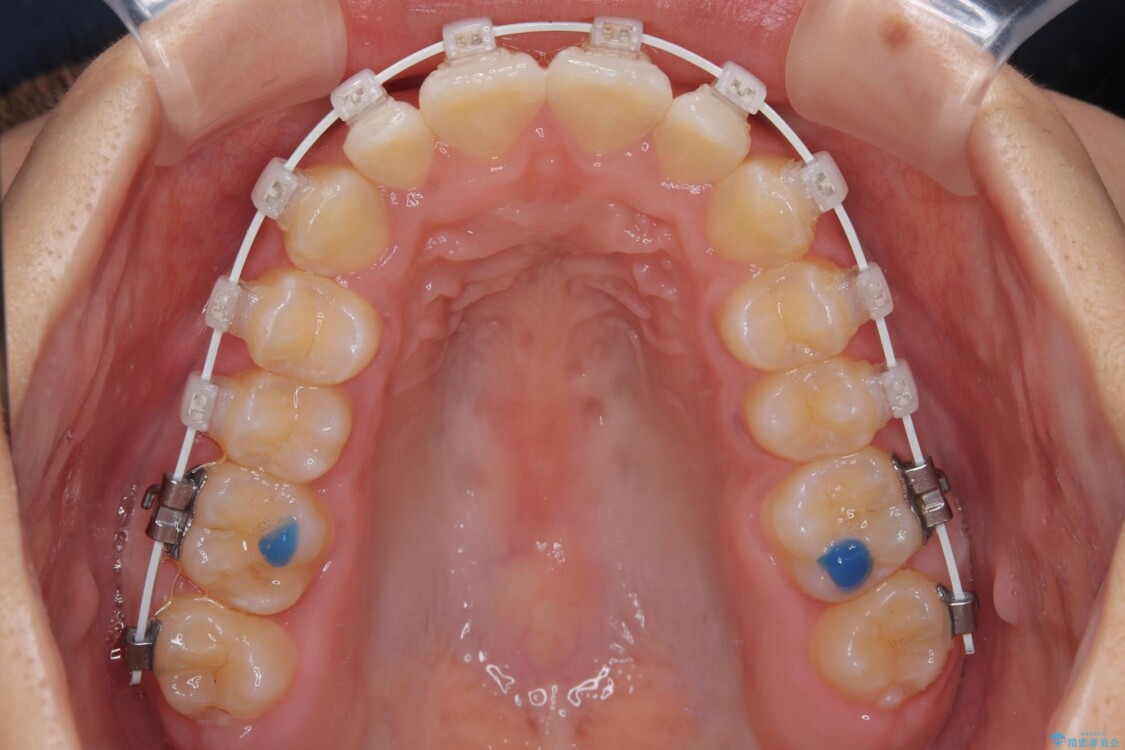

審美装置

・アーチを側方に拡大して歯が並ぶスペースを確保

・抜歯は避け、非抜歯での対応

・目立ちにくい審美装置による矯正

・治療期間をできるだけ短縮するために、綿密な装置管理と協力体制を構築

治療途中

• 目立ちにくい表側装置で1年完了!狭いアーチを側方拡大し前歯のデコボコを整えた症例 治療途中画像